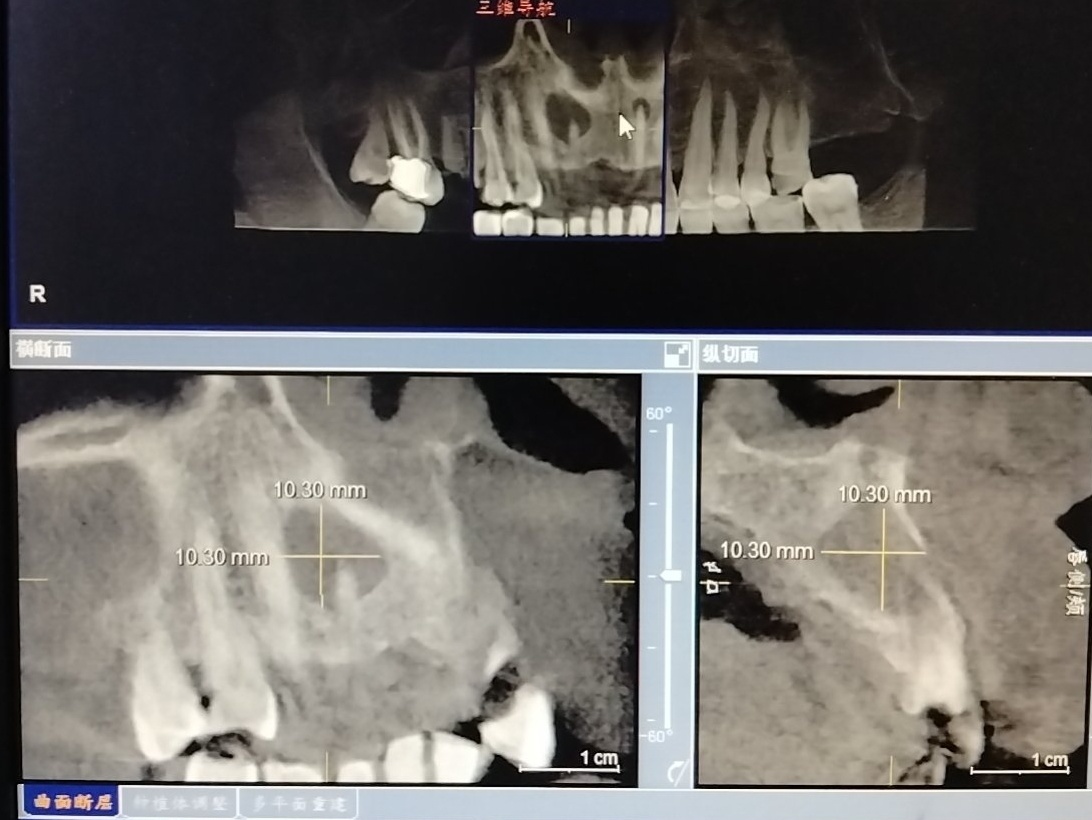

大家好我就是那个干口腔颌面外的制作组长Plones,我也很好奇相差这么远的两个领域是怎么样一个成为主业另一个从爱好发展成副业人的。但我确实同时干公立三甲的口腔外科主治和独立游戏制作(也可能是医院基层🐮🐴收入太低了不打工生存不了),现在因为医科大教师少我们是